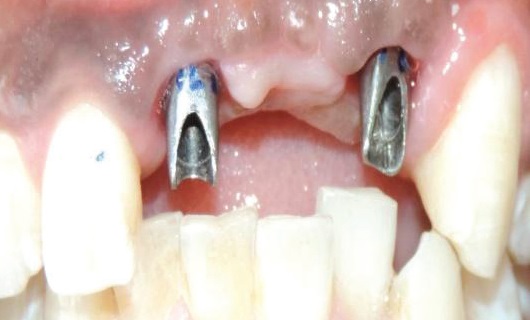

Tính năng thứ 3: Tái lập thân răng đúng chuẩn giải phẫu nhờ sử dụng Abutment Customized.

Thân răng, vừa có vai trò truyền tài và cảm biến ăn nhai, vừa có vai trò định hình ổn định cho mô nha chu. Để tối ưu về mặt truyền lực, thân răng có hình dạng rất khác nhau giữa răng cửa và răng hàm, răng hàm trên và răng hàm dưới.

Đối với phương pháp trồng răng implant kiểu cũ, trụ phục hình được sử dụng là trụ phục hình sản xuất sẵn, có duy nhất một hình dạng là hình trụ thuôn thiết diện tròn, khác xa với hình thể của thân răng thật, do đó nó không thể tạo ra hình thể thân răng lý tưởng, không đảm trách hết vai trò của một thân răng.

DCT sử dụng trụ phục hình cá nhân hóa (Customized Abutment), được sản xuất bằng cách may đo phù hợp với hình thể giải phẫu lý tưởng của từng răng, từng người. Customized Abutment có hình thể giống đúc thân răng lý tưởng, từ đó có thể nâng đỡ tốt mô nha chu, truyền lực tốt và đặc biệt việc sử dụng vật liệu cao cấp giúp lợi có thể kết nối trực tiếp lên bề mặt trụ, từ đó tạo ra hàng rào sinh học ngăn không cho vi khuẩn từ môi trường miệng xâm nhập xuống phía dưới.

Một trường hợp sử dụng trụ phục hình các nhân hóa bằng zirconia.

So sánh với một trường hợp sử dụng trụ phục hình sản xuất sẵn (đã được mài mặt ngoài để xóa hình thể tròn).